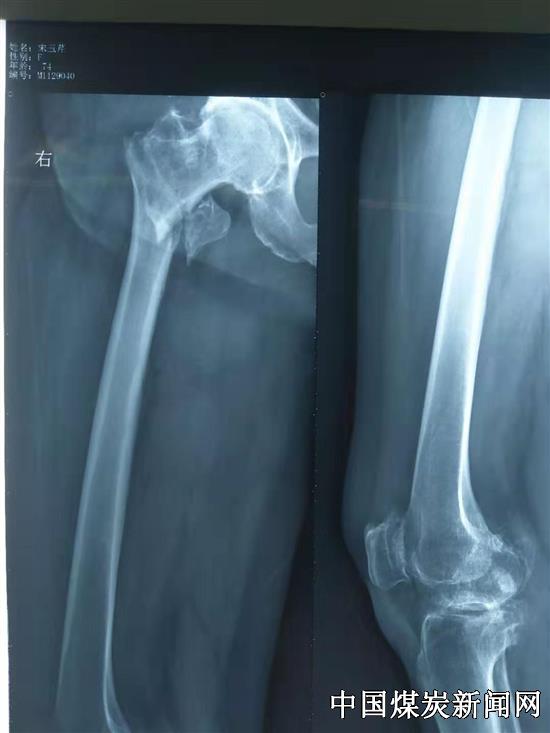

邯矿总医院骨外科每年为几十名高龄骨折的患者及时行手术治疗,其中不乏80岁以上的高龄患者。股骨粗隆间骨折常见于老年人,特别是老年女性,由于骨质疏松等原因出现骨脆性增加、骨强度降低更容易患股骨粗隆间骨折,保守治疗,高龄患者需长期卧床,容易出现肺炎、褥疮、深静脉血栓形成等并发症,严重影响生活质量及寿命。

邯矿总医院外科医疗团队在陈志东主任带领下积极开展相关研究,对股骨粗隆间骨折采取闭合复位PFNA内固定术,手术时间一般在30分钟左右,创伤小,降低了手术风险。为广大老年患者带来福音。